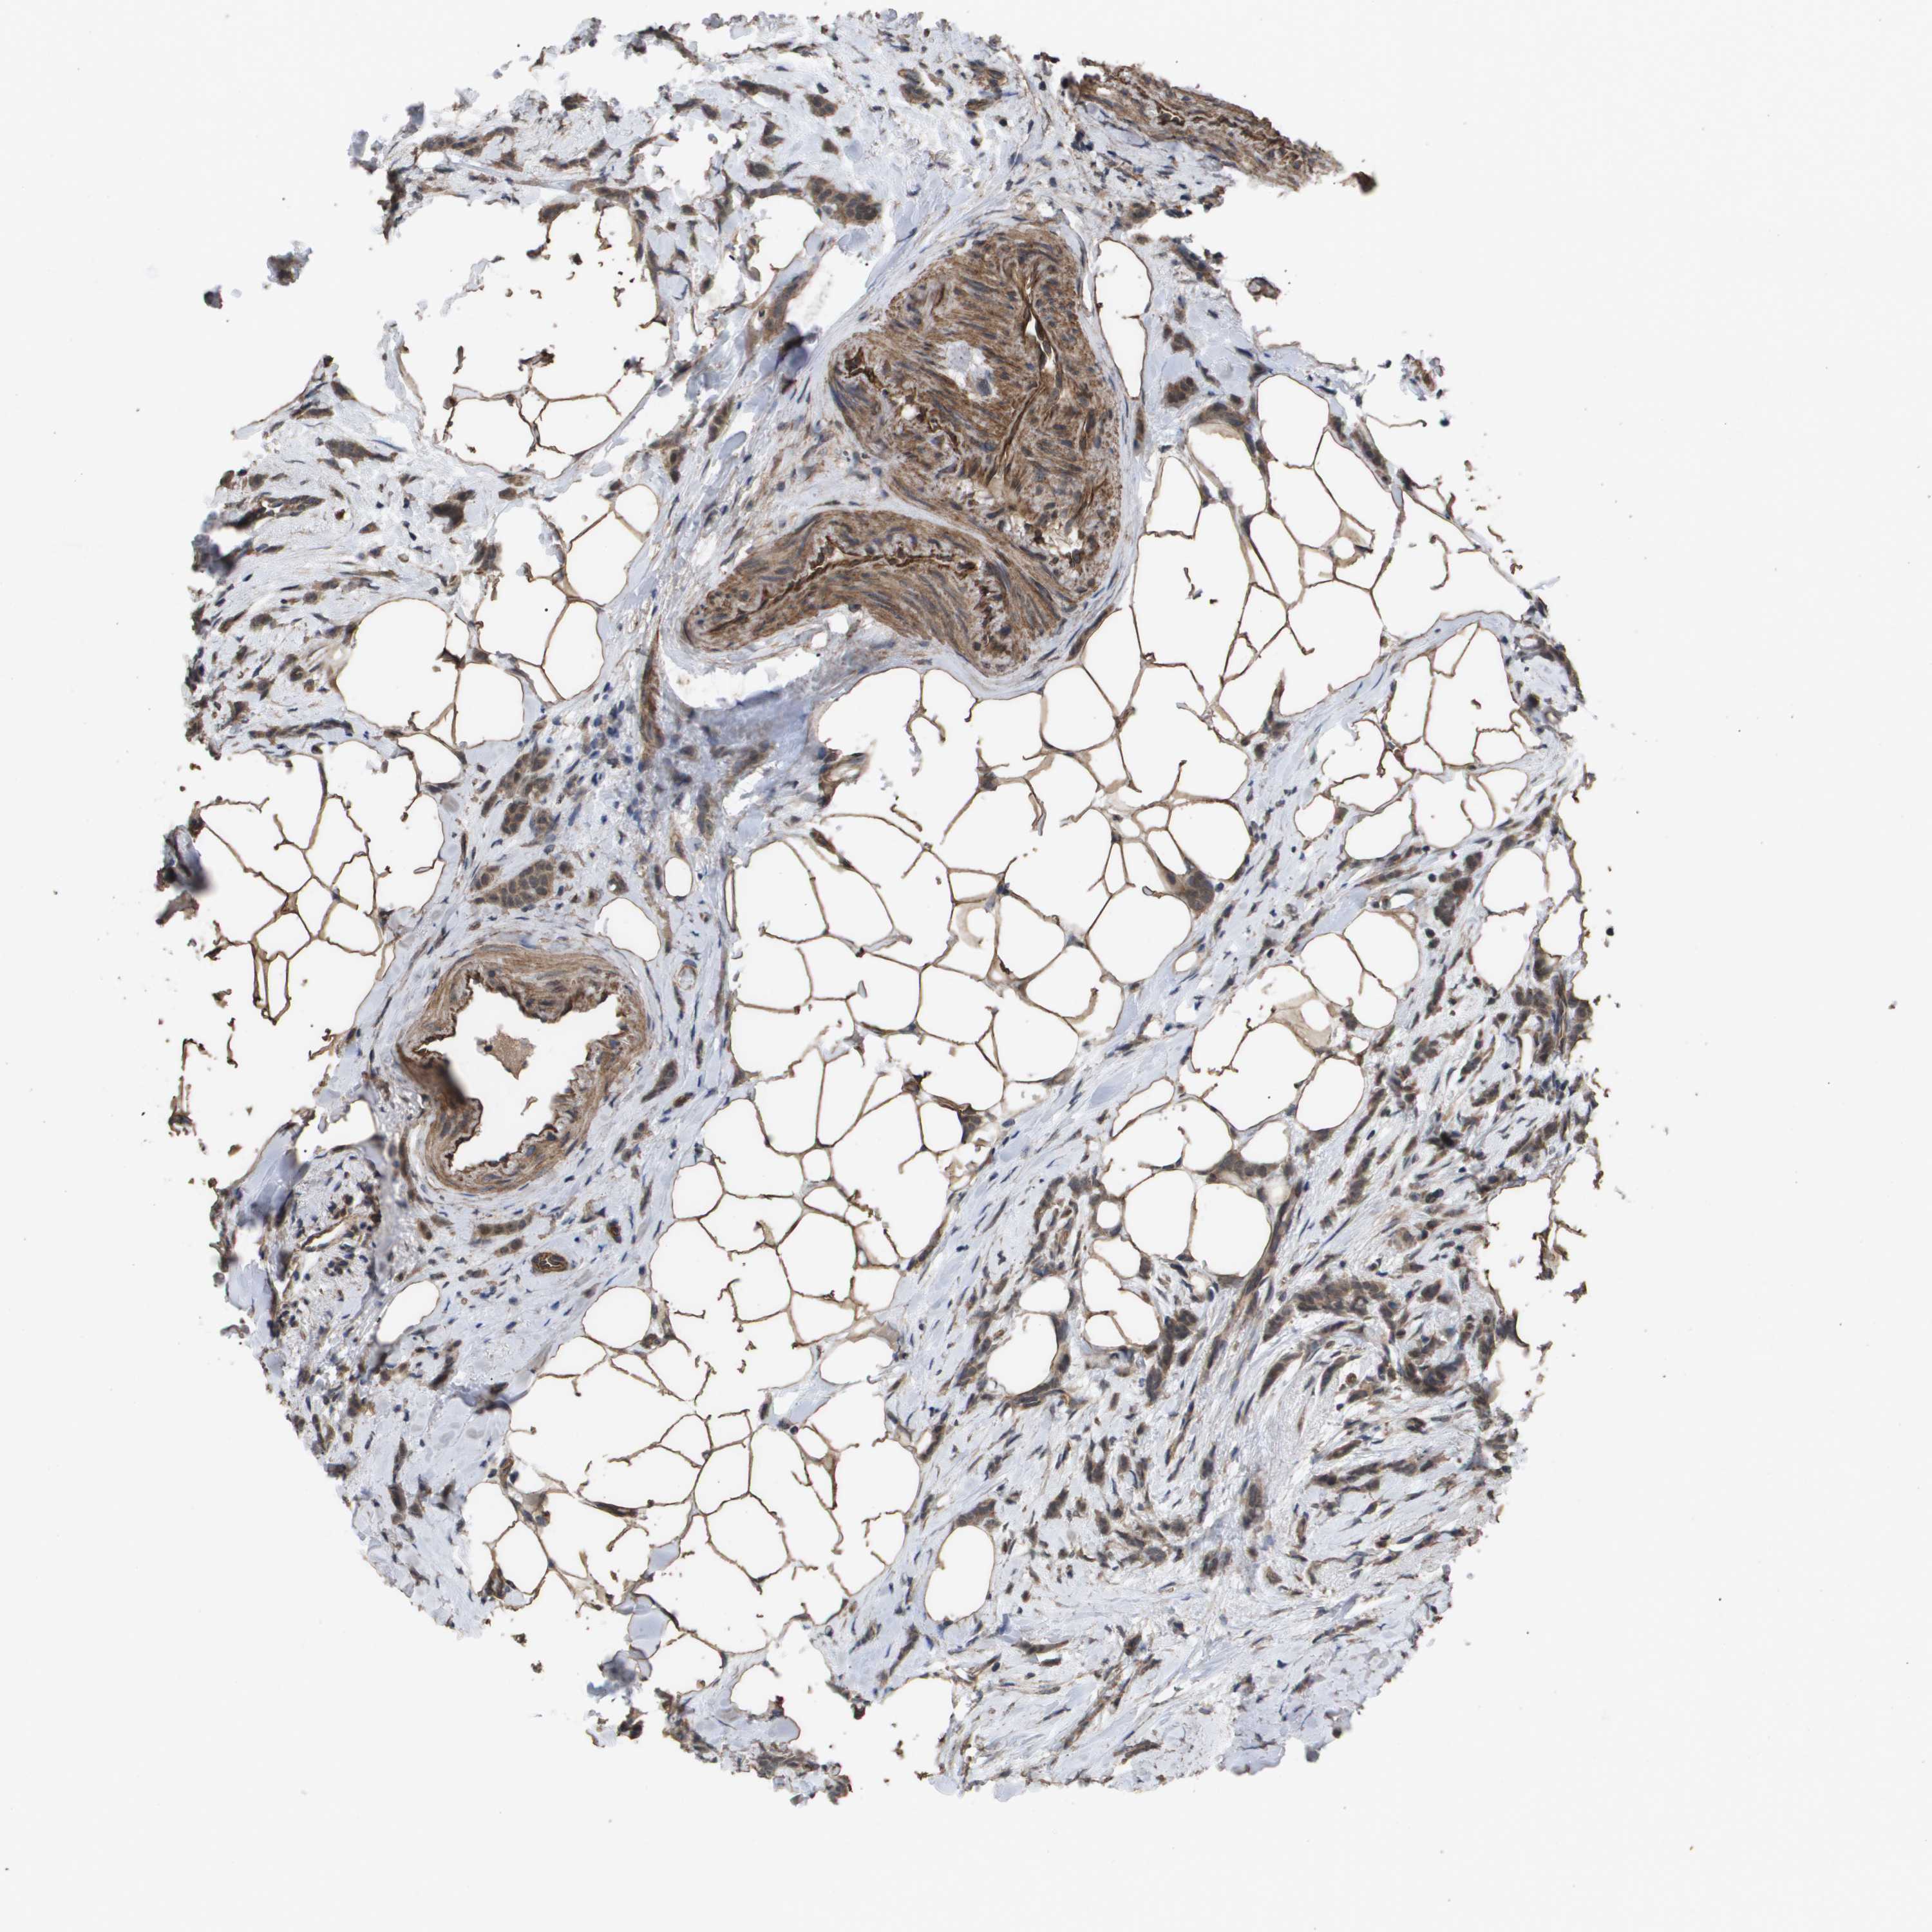

BRCA TCGA BRCA VALIDATION PROTEIN EXPRESSION